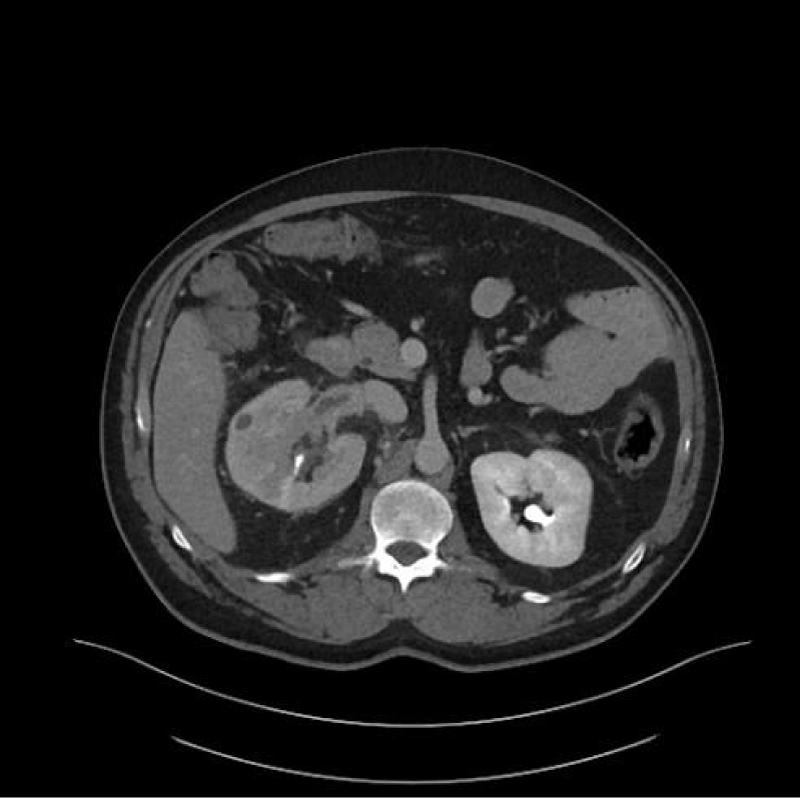

Renal cell carcinoma (RCC) is the ninth and fourteenth most common carcinoma in men and women respectively, alongside being the most lethal urological malignancy. RCC accounts for up to 90% of all kidney cancers, and up to 80% of all SRM. RCC constitutes Clear Cell (Figures 4-6), 75%, Papillary, around 15% to 20%, Chromophobe (Figures 7-9), 5% and other rarer subtypes. Clear Cell is the most common variant with the worst prognosis as it commonly presents at an advanced stage. Papillary type is more frequent in smaller lesion sizes [1,2,3,9-15].

Download Image

Figure 7: Right renal Chromophobe RCC of the lower pole, with solid and cystic components.

Figure 8: Chromophobe RCC of the lower pole of left kidney.

Figure 9: Chromophobe RCC of the lower pole of right kidney.